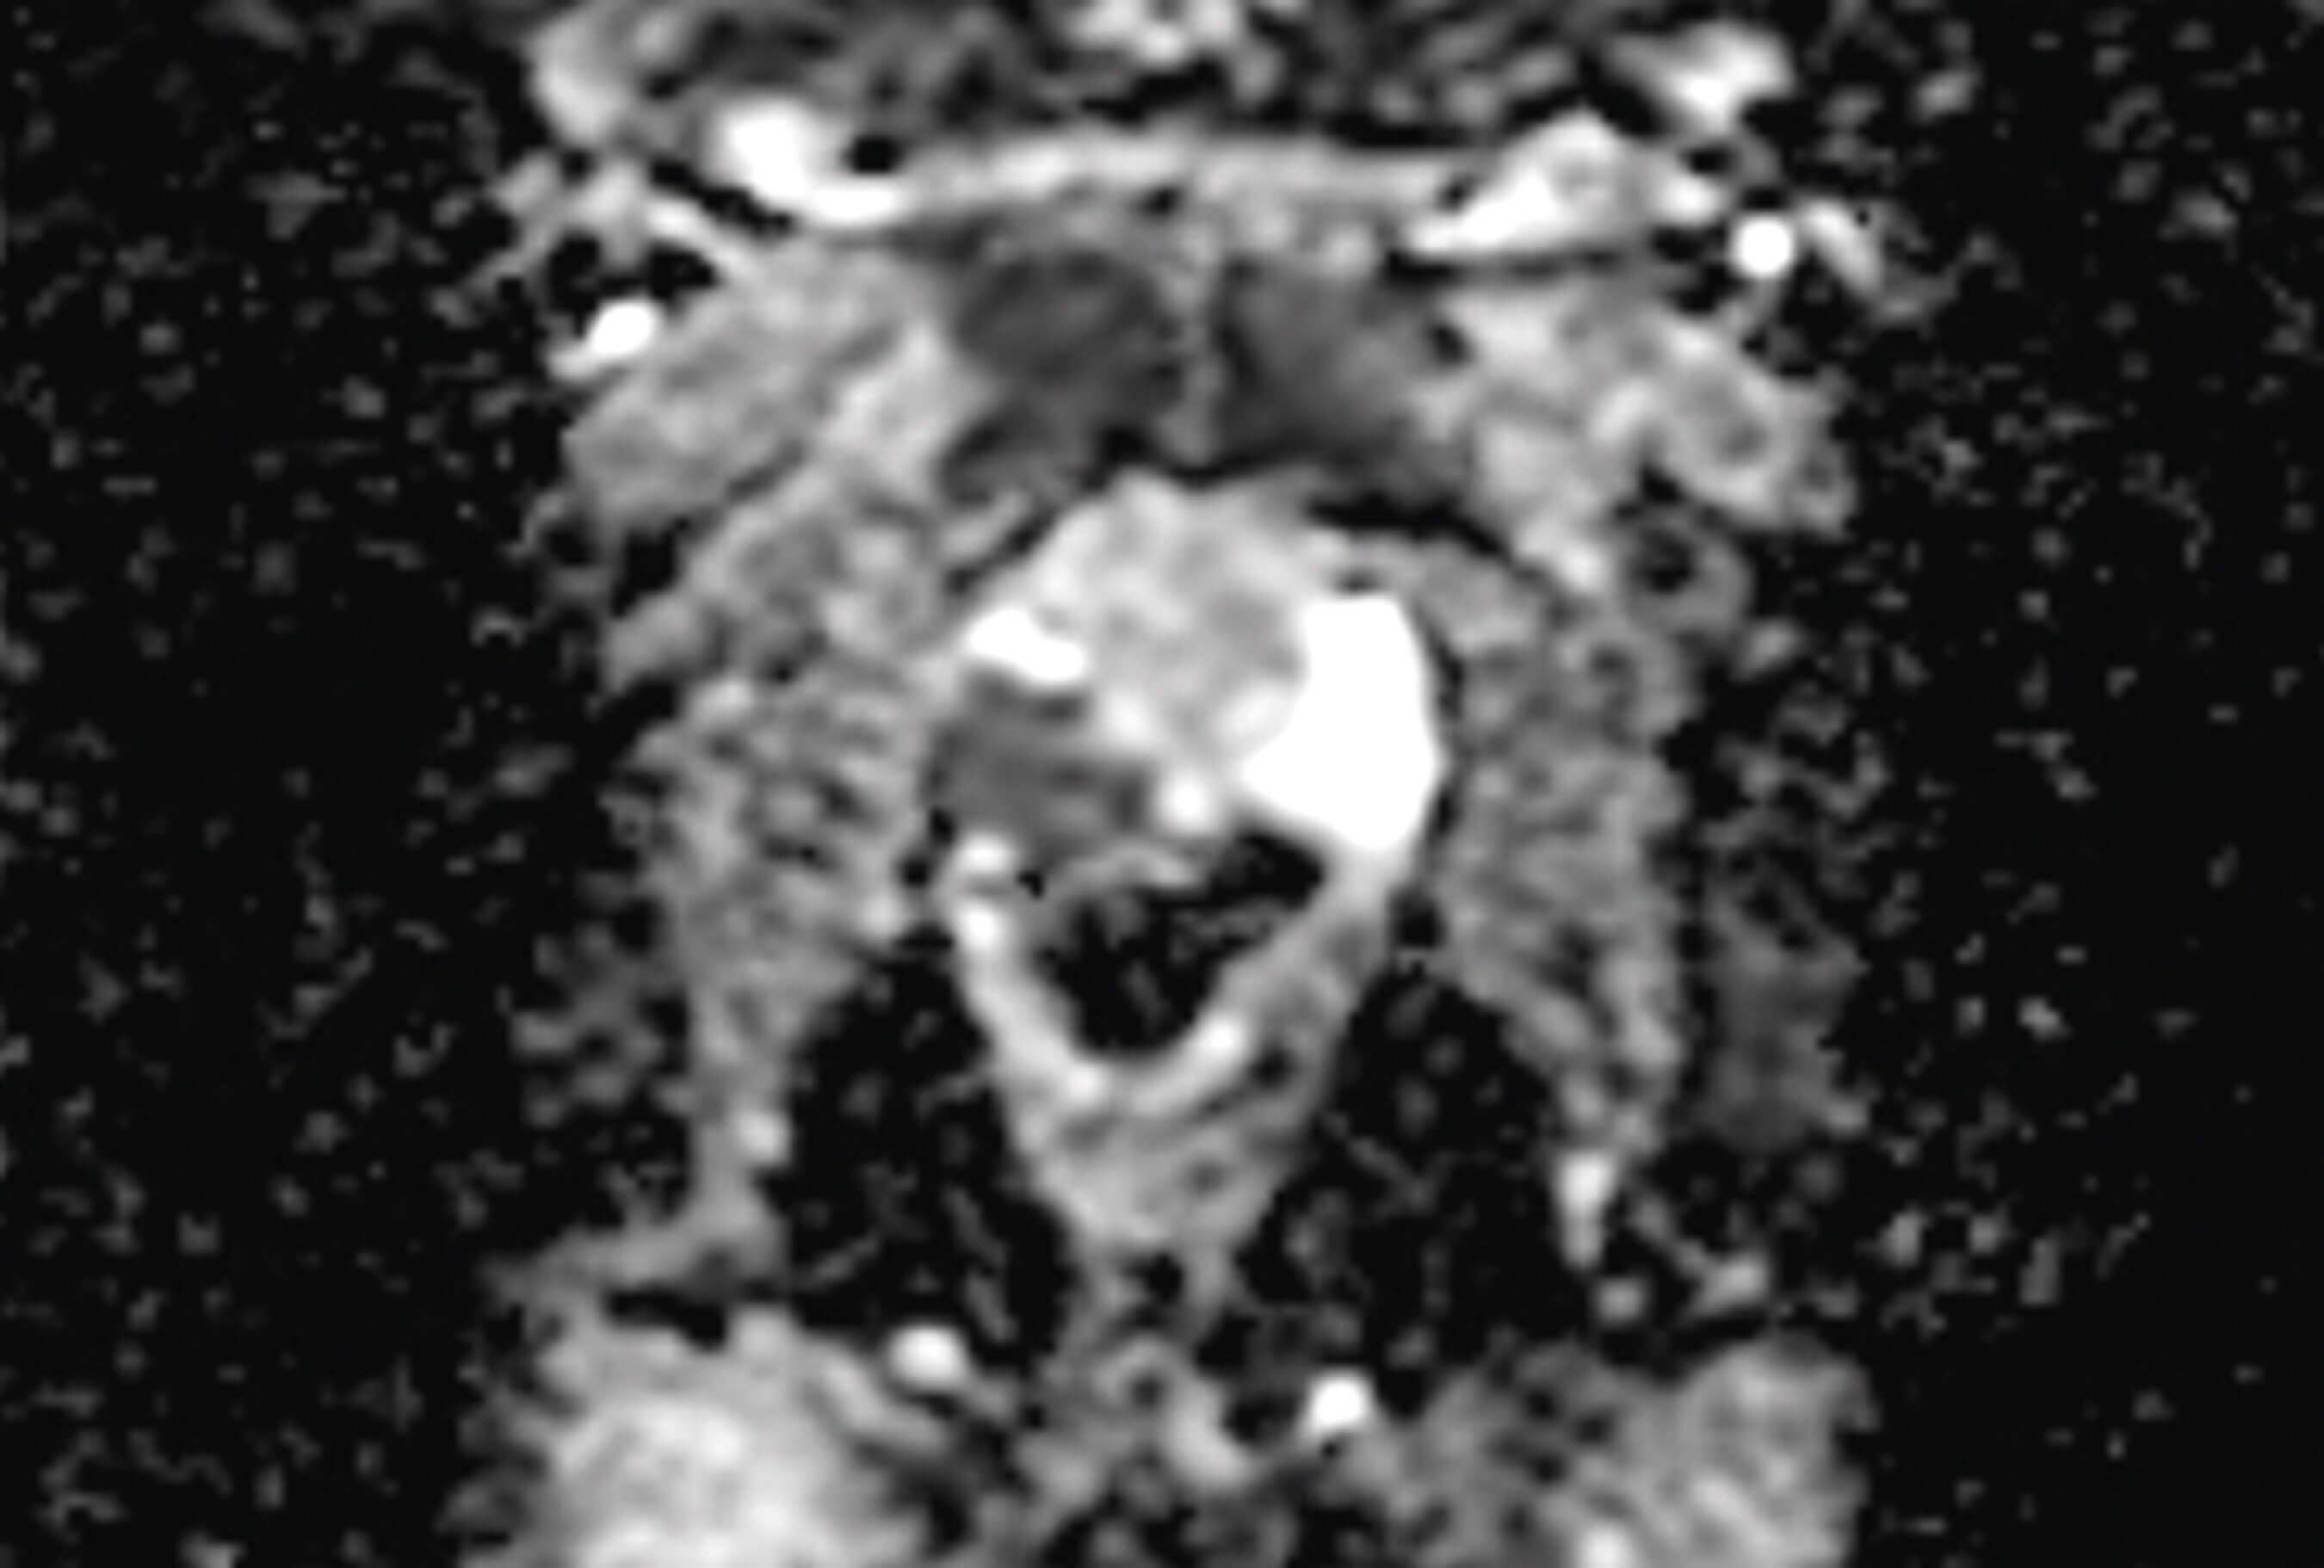

Figure 2 is the diffusion weighted imaging (DWI). DWI refers to how easily water diffuses across the cells. The diffusion of water is impeded by the increase in number of cells and the tumour matrix (i.e. restricted diffusion). Therefore, cancer cells lead to increased restricted diffusion. This lesion would be considered Prostate Imaging Reporting & Data System (PIRADS) 5.

Figure 3 is the apparent diffusion coefficient (ADC) sequence. Using complex equations, ADC is derived from DWI. Prostate cancer appears dark on ADC sequence as seen here.